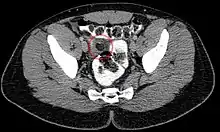

Ultrasound and CT scans are the normal means of positive diagnosis of Epiploic Appendagitis. Ultrasound scans show "an oval, non-compressible hyperechoic mass with a subtle hypoechoic rim directly under the site of maximum tenderness".[4] Normally, epiploic appendages cannot be seen on CT scan.[4] After cross-sectional imaging and the increased use of abdominal CT for evaluating lower abdominal pain, EA is increasingly diagnosed. Pathognomonic CT scan data represent EA as 2–4 cm, oval shaped, fat density lesions, surrounded by inflammation. Contrasting with diverticulitis findings, the colonic wall is mostly unchanged.